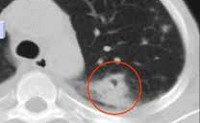

Диагностика кандидоза легких включает проведение рентгенографии и КТ легких, бронхоскопии, микроскопии мокроты, культурального и серологического исследований бронхоскопического материала и крови. Проявления кандидоза легких не патогномоничны, но могут сопровождаться кандидозным поражением других органов, анамнестическими сведениями о предшествующей кандида-инфекции. Аускультативная картина часто скудная, без ясных симптомов, иногда выслушиваются сухие и влажные мелкопузырчатые хрипы.

Рентгенологически может выявляться усиление легочного рисунка в прикорневых зонах на ранней стадии, позднее - множественные мелкие инфильтраты с нечеткими контурами в нижних и средних долях. Определяются реактивные изменения в легких, лимфатической системе корня и средостения; плевральный выпот, участки гнойного расплавления (абсцессы). Характерно затяжное течение и относительно быстрое изменение объективных данных со стороны легких и плевры (появление и исчезновение тонкостенных полостей, выпота), симптоматики (от хронического бронхита и пневмонии - до плеврита и абсцесса), а также результатов функциональных тестов.